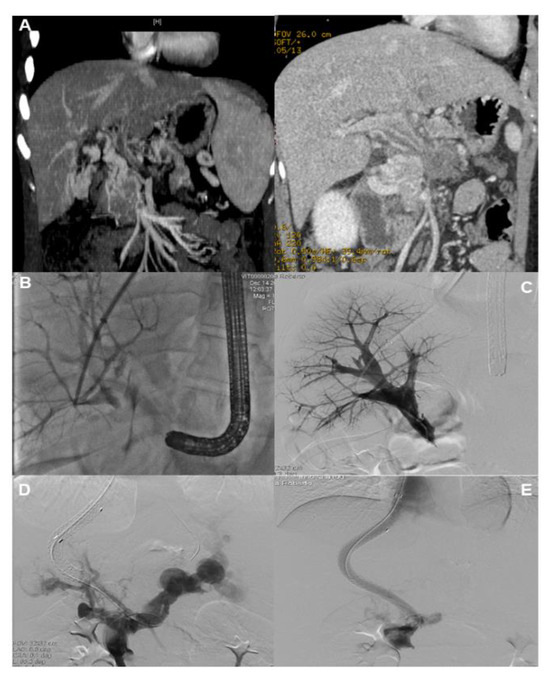

- Bissonnette, J.; Garcia-Pagan, J.C.; Albillos, A.; Turon, F.; Ferreira, C.; Tellez, L.; Nault, J.C.; Carbonell, N.; Cervoni, J.P.; Abdel Rehim, M.; et al. Role of the transjugular intrahepatic portosystemic shunt in the management of severe complications of portal hypertension in idiopathic noncirrhotic portal hypertension. Hepatology 2016, 64, 224–231. [Google Scholar] [CrossRef] [PubMed]

- Lv, Y.; Li, K.; He, C.; Luo, B.; Zhang, B.; Liu, H.; Wang, Z.; Guo, W.; Wang, Q.; Chen, H.; et al. TIPSS for variceal bleeding in patients with idiopathic non-cirrhotic portal hypertension: Comparison with patients who have cirrhosis. Aliment. Pharmacol. Ther. 2019, 49, 926–939. [Google Scholar] [CrossRef]

- Regnault, D.; d’Alteroche, L.; Nicolas, C.; Dujardin, F.; Ayoub, J.; Perarnau, J.M. Ten-year experience of transjugular intrahepatic portosystemic shunt for noncirrhotic portal hypertension. Eur. J. Gastroenterol. Hepatol. 2018, 30, 557–562. [Google Scholar] [CrossRef] [PubMed]